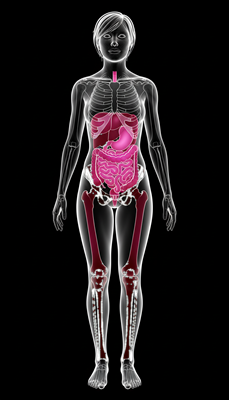

Powerful Antioxidant & Anti-inflammatory Effects

Polyphenols, phenolics, flavonoids, and tocopherols neutralize free radicals, reduce oxidative stress, and provide anti-aging benefits. Prevents cellular damage linked to chronic diseases.

Anti-Cancer Potential

In vitro studies show cytotoxic effects against various cancer cell lines, linked to stigmasterol, β-sitosterol, and squalene.

Cardiovascular Support

Unsaturated fatty acids (especially linoleic acid) may help lower cholesterol levels and reduce risk of heart disease.

Antimicrobial Activity

Extracts show activity against Gram-positive (e.g., Staphylococcus aureus) and Gram-negative (e.g., Pseudomonas aeruginosa) bacteria.

Antidiabetic & Nephroprotective Effects

Black truffle modulates oxidative stress and cytokines via Nrf2 pathway, showing antidiabetic and kidney-protective activity.

Immune System Support

Polysaccharides help regulate and strengthen immunity against infections and disease.

Digestive Health

High dietary fiber (7–15g/100g) promotes regular bowel movements and prebiotic effects.

Neurological & Aphrodisiac Effects

Anandamide ("bliss molecule") supports mood & appetite regulation. Androstenol historically used as aphrodisiac via aroma stimulation.

Bone Health

Ergosterol (vitamin D precursor) supports calcium absorption and bone mineralization.